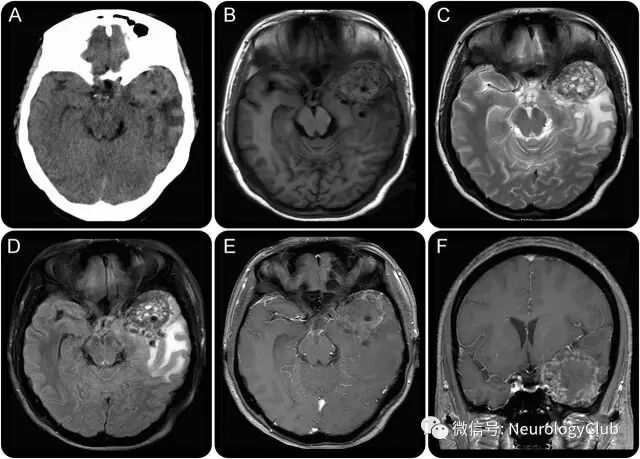

(图1:A:CT可见不均匀的含有多发低密度囊性变的实体肿块伴周围广泛水肿;B-D:T1WI,T2WI和FLAIR可见不均匀信号的球形肿块伴多发中央囊性坏死区;E-F:增强MRI可见病灶边缘不规则强化)